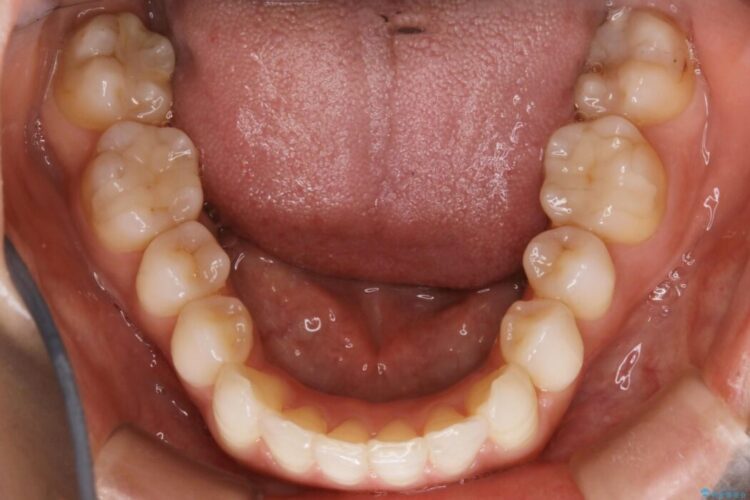

軽度のガタつきと不正咬合が見受けられましたので、インビザラインでの矯正治療を計画しました。

既定のインビザラインの装着時間を守っていただけたこともあり整ったアーチとなりました。

特に気にされていた噛み合わせは改善されご満足いただけました。